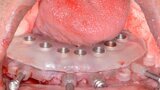

Fig. 13: Implants with corresponding multi-unit abutments.

Fig. 15: Insertion of provisional restoration.

Fig. 18: Implants with corresponding multi-unit abutments.